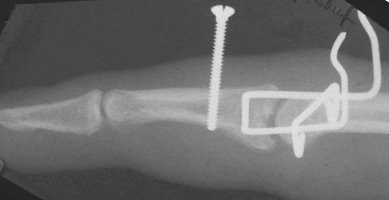

Clinical Example: PIP fracture dislocation treated with force couple splint

Proximal interphalangeal joint fracture dislocation is a common and difficult injury. There are many possible treatment techniques. Here, the force couple splint method was used.